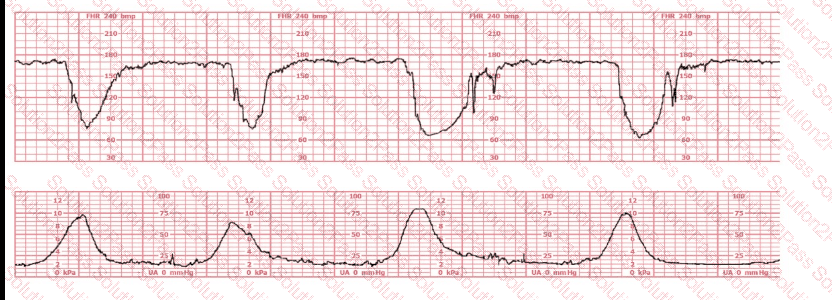

This fetal heart rate tracing is obtained upon the woman's admission to labor and delivery. This tracing is most reflective of:

The baseline fetal heart rate in this tracing is:

This fetal heart rate tracing represents:

The tracing shown is a:

The decelerations seen in the fetal monitoring tracing shown are best described as: